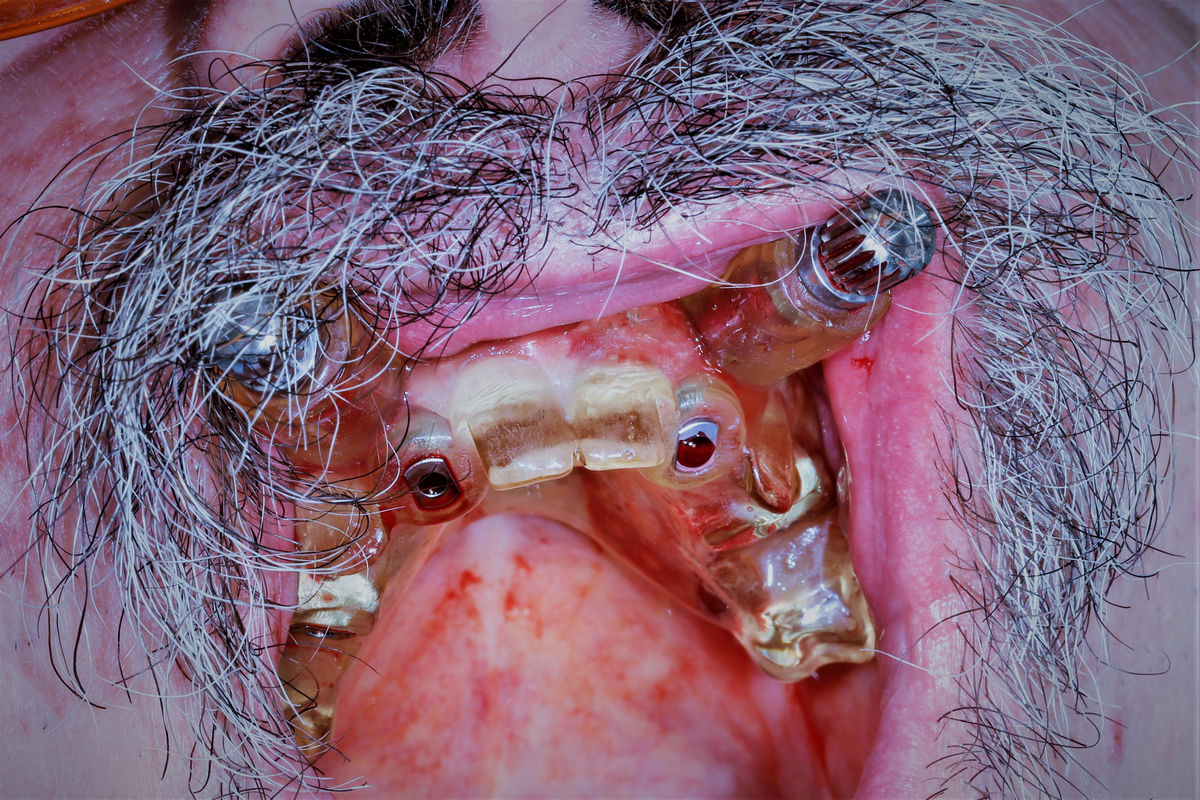

Chirurgia implantologiczna to temat wiodący 5 Sesji X Sezonu Practiculum Implantologii, która się odbyła 23-24 października 2020 roku. Bierze w nim udział 16 adeptów implantologii stomatologicznej. Zabiegi z udziałem Pacjentów jak zwykle poprzedziło omówienie i planowanie, tym bardziej, że zgodnie z planem wykonana została implantacja z wykorzystaniem szablonu chirurgicznego, który przygotowało laboratorium dentystyczne Wiligała Lab. Kursanci wykonywali szereg zabiegów implantologicznych i chirurgicznych oraz regeneracyjnych z zastosowaniem PRF, w tym sinus lift. Przeprowadzali je pod kierunkiem Lidera Umiejętności Implantologicznych dr n.med. Violetty Szycik, która wysoko oceniła wykonanie zabiegów.